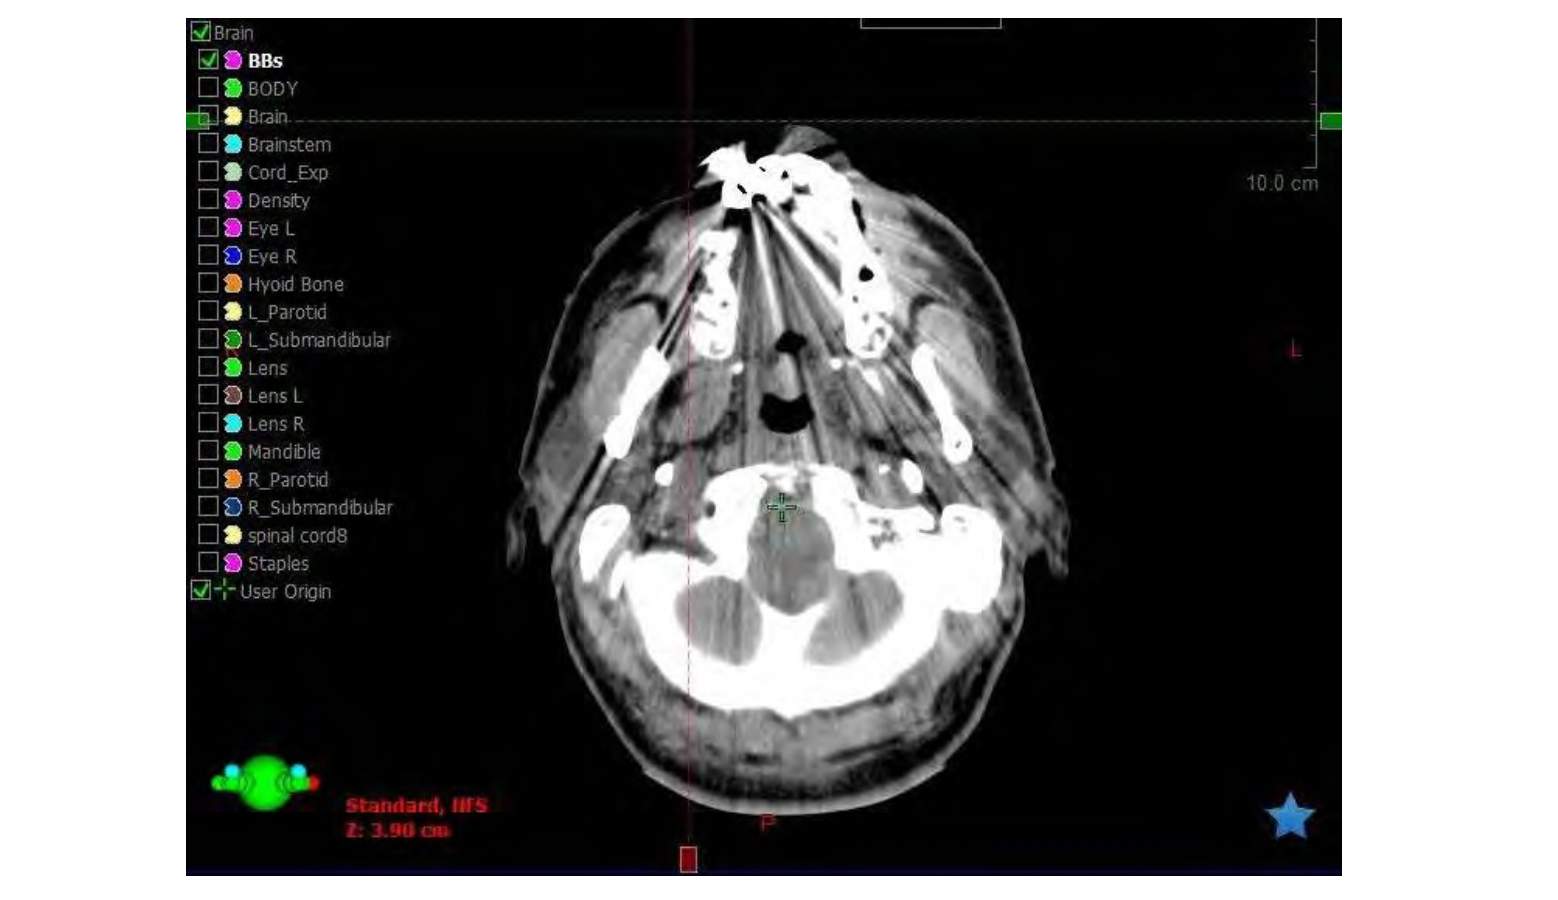

Here, we will contour the structures relevant to the whole brain radiotherapy (WBRT) treatment plan.

For the brain contour, we often use the segmentation wizard and refine the structure with post-processing.

Spinal Cord

For the cord contour, we often delineate the spinal canal inferiorly from the foramen magnum down to about C3-C4. Skipping every other slice and interpolating may help speed up the process. Remember to review the contour after using automated tools.

BBs

Contour the BBs.

Density Overrides

If there are artifacts or other materials that need to be overridden, this is an appropriate time to do so.